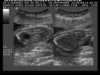

AVF within kidney